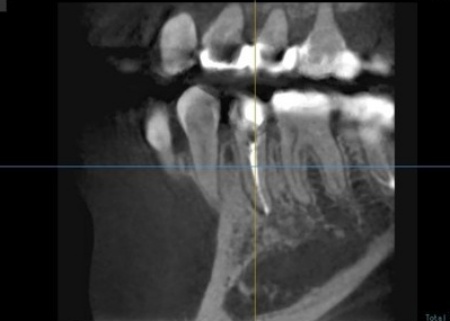

拝見したところ、右下奥歯(第2小臼歯)には保険診療の白い被せ物であるCAD/CAM冠が装着されていましたが、破折して外れている状態でした。

右下奥歯を詳しく検査をした結果、過去に細菌感染した神経を取り除いてから薬を詰める「根管治療」が行われていることがわかりました。

ただ、その手前の右下奥歯(第1小臼歯)では、歯の内部に細菌が侵入して炎症が生じており、歯根の先に膿が溜まる根尖(こんせん)病巣を発症しています。

まず、血液や唾液に含まれる細菌が根管内に入るのを防ぐため、ゴム製のシートであるラバーダムで患部周辺を覆って治療部位だけを露出させ、マイクロスコープで確認しながら感染部位を丁寧に除去しました。

根管内が清潔になったら、再び細菌が入り込まないようにしっかりと薬を詰めて封鎖後、レントゲン撮影で根尖病巣の治癒を確認しました。